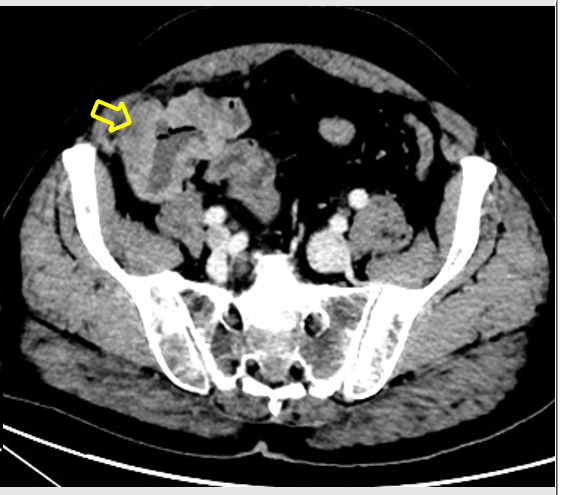

HALLAZGOS RADIOLÓGICOS